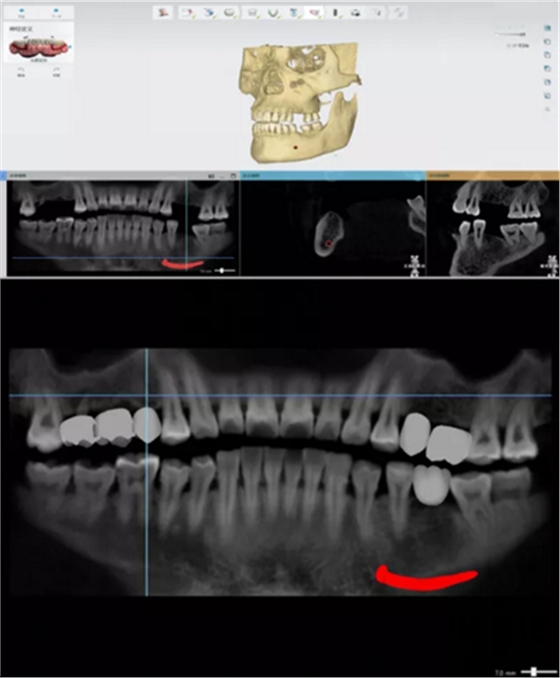

繪制下頜神經(jīng)管

植體植入設(shè)計